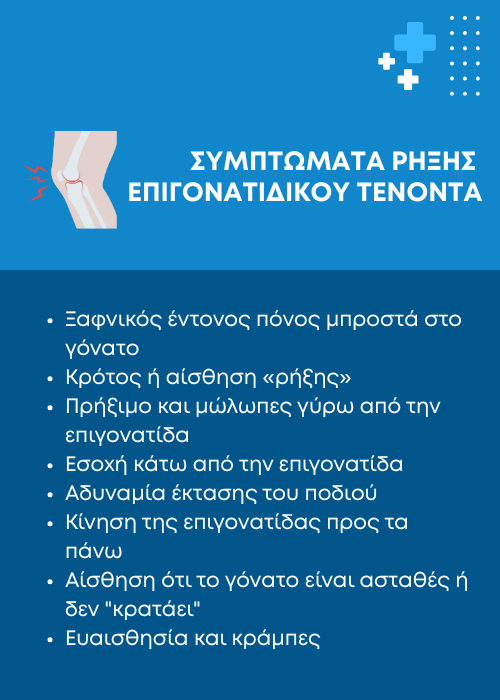

Συμπτώματα ρήξης

Όταν ένας επιγονατιδικός τένοντας ρήγνυται, συχνά αισθάνεστε ρήξη ή κροτάλισμα και μπορεί να μην μπορείτε να ισιώσετε το γόνατό σας. Επιπλέον συμπτώματα περιλαμβάνουν:

- Πόνο: Έντονο πόνο στο μπροστινό μέρος του γόνατος.

- Οίδημα: Πρήξιμο γύρω από την επιγονατίδα.

- Μια εσοχή στο κάτω μέρος της επιγονατίδας σας όπου ρήγνυται ο επιγονατιδικός τένοντας

- Μώλωπες

- Ευαισθησία

- Κράμπες

- Η επιγονατίδα σας κινείται προς τα πάνω στον μηρό επειδή δεν είναι πλέον αγκυρωμένη στην κνήμη σας

- Δυσκολία στην κίνηση: Δυσκολία στην κάμψη ή την έκταση του γόνατος.

- Αίσθημα ασταθούς γόνατος: Αίσθηση ότι το γόνατο "δεν κρατάει" ή "δεν είναι σταθερό".

• Ποια είναι τα συμπτώματα ρήξης του επιγονατιδικού συνδέσμου;

Ξαφνικός πόνος στο γόνατο, οίδημα, αδυναμία έκτασης του ποδιού και ενίοτε ένα «κρακ» τη στιγμή του τραυματισμού. Συχνά, το άτομο δεν μπορεί να σταθεί ή να περπατήσει σωστά.